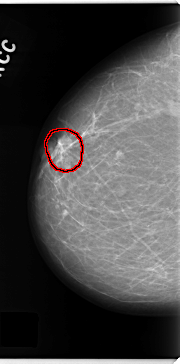

FILE: C_0155_1.RIGHT_MLO.OVERLAY

TOTAL_ABNORMALITIES 1

ABNORMALITY 1

LESION_TYPE MASS SHAPE LOBULATED MARGINS ILL_DEFINED

ASSESSMENT 5

SUBTLETY 4

PATHOLOGY MALIGNANT

TOTAL_OUTLINES 1

BOUNDARY